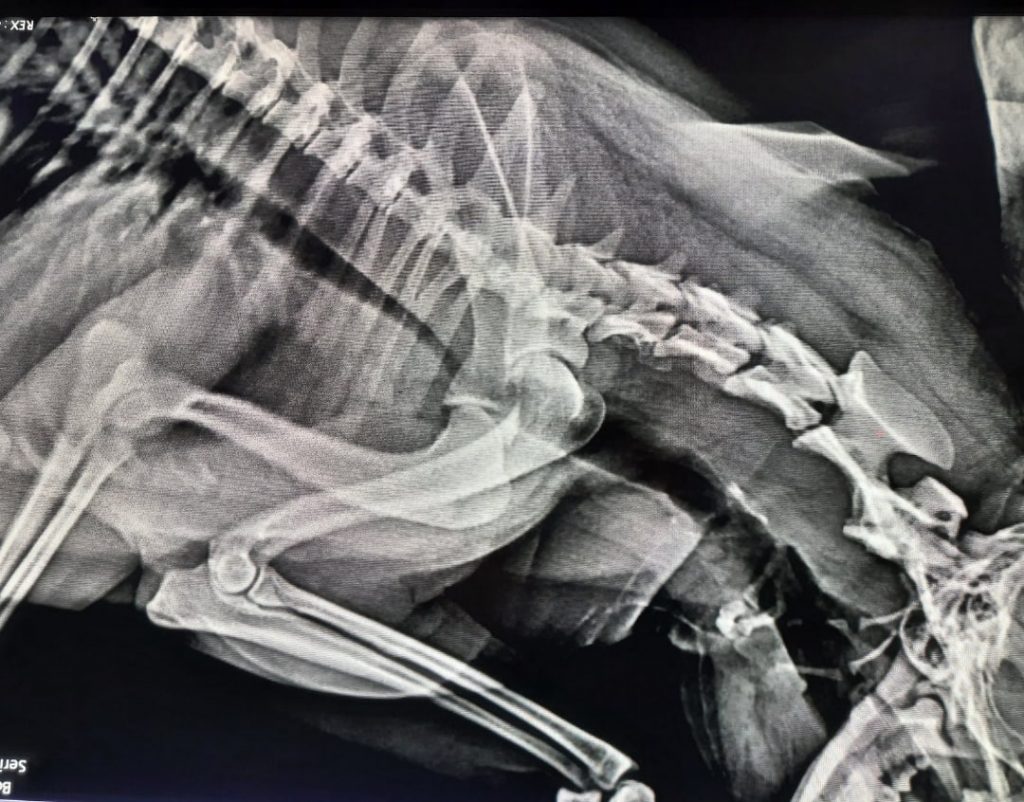

Коллапс трахеи форум